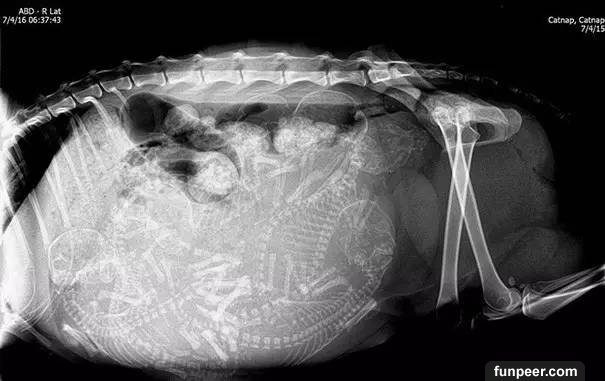

貓媽媽的X照片是這樣的

另一張貓的照片,有許多小貓

最後,又是貓,有五個生命將誕生!